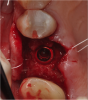

The patient wanted an implant-supported crown to restore the right mandibular first molar, which had been extracted after recurrent caries, endodontic treatment, and development of a periapical lesion. The site was grafted with bone grafting material and a biological membrane and allowed to heal for 6 months. A periapical radiograph was then taken (Figure 6), which showed the socket areas to be well condensed, with mature-looking bone. A CBCT scan was taken to facilitate implant-placement planning.

Two impressions were made: one to serve as a record of the edentulous site, and the second for use in making a stone diagnostic cast. The stone cast was scanned, and a stereolithographic model of the restoration was printed and mounted on the cast (Figure 7). Scan data from this was merged with the CBCT to enable 3D guided surgical planning. The location of the inferior alveolar nerve canal was identified, and an ample amount of bone above it was evident. A 12-mm-long, 4.8-mm-diameter implant was chosen for placement.

Fig 6. Periapical radiograph, single missing tooth.

Figure 6